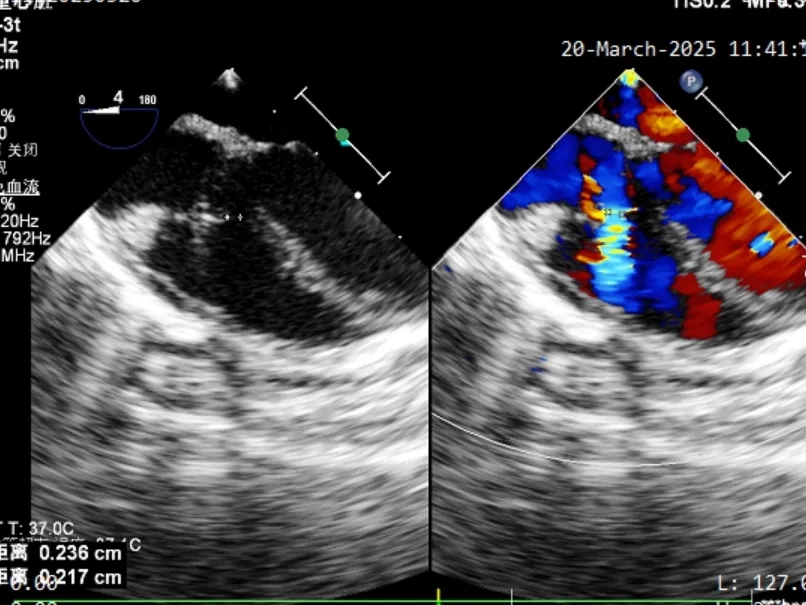

缺损情况:术中食道超声复测为膜部瘤型室缺,瘤体基底宽约7.6mm,两处破口分别宽约1.3mm及2.3mm。

术中超声复测

膨出瘤基底部宽约7.6mm

两处破口分别宽约2.3mm及1.3mm

术中食道超声复测发现本例为膨出瘤型室缺并伴有多破口,瘤体基底宽约7.6mm, 两处破口分别宽约1.3mm和2.3mm。由于金属封堵器盘面展开易受膨出瘤限制,可能无法完全覆盖所有破口,存在残余分流风险。而全降解封堵器凭借其良好的柔韧性,植入后既能够自适应膨出瘤复杂的结构形态和组织运动,又可确保完全封堵。术者经综合考虑后,最终选择使用ABFDQ-I 5规格的全降解封堵器进行封堵。术后超声显示,封堵器形态良好,封堵完全,无残余分流。术后1个月随访,封堵器位置形态良好,患者恢复情况良好。